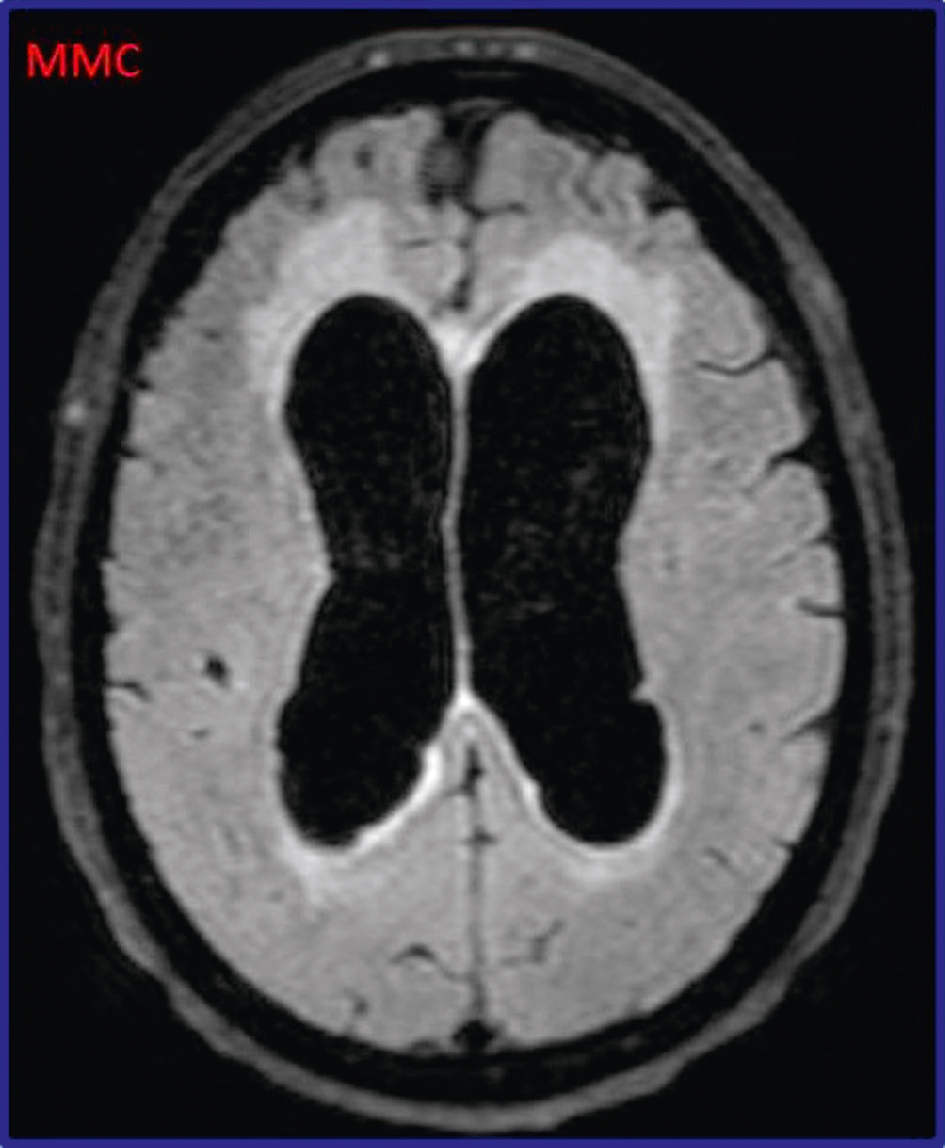

Le diagnostic repose sur l’IRM cérébrale qui montre une dilatation tétraventriculaire avec peu d’atrophie corticale et des plages d’hyposignal T2 autour des ventricules, traduction de la résorption trans-épendymaire du LCS (fig. 19.1).

Hydrocéphalie chronique : IRM cérébrale. Dilatation tétraventriculaire, avec atrophie corticale comparativement modérée.

Cette image en coupes axiales d’IRM cérébrale montre une dilatation marquée et symétrique des ventricules latéraux, sans élargissement cortical périphérique proportionnel, ce qui évoque une hydrocéphalie chronique à pression normale. Le signal est homogène au sein du liquide céphalorachidien intraventriculaire, et les cornes frontales comme occipitales sont nettement arrondies, accentuant la forme en oreilles de Mickey caractéristique. L’élargissement ventriculaire s’effectue aux dépens du parenchyme péri-ventriculaire, sans signes visibles d’œdème actif ou de processus expansif. Cet aspect radiologique est évocateur d’un trouble de la résorption du liquide céphalorachidien, souvent associé à une triade clinique incluant troubles de la marche, troubles cognitifs et incontinence urinaire, typique du tableau de l’hydrocéphalie chronique de l’adulte.